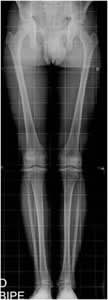

Fig 99. Longitud de extremidades.

Rx AP. La longitud de las extremidades es simétrica.

La dismetría de los miembros inferiores generalmente ocurre por acortamiento, que desencadena mecanismos compensatorios. Es común el acortamiento de pocos milímetros sin repercusión clínica y con predominio en el lado derecho. Entre 5 y 20 mm de diferencia, hay basculación de la pelvis. Mas de 20 mm ocasiona escoliosis vertebral y deformidad en rodillas y tobillos. (3). (Fig 100 y 101).

Fig 100. Desbalance pélvico.

Rx AP. Acortamiento izquierdo, con elevación de la cresta iliaca derecha. (Línea continua).

Fig 101. Desbalance pélvico.

Rx AP. Acortamiento derecho, con elevación de la cresta iliaca izquierda y escoliosis lumbar derecha.